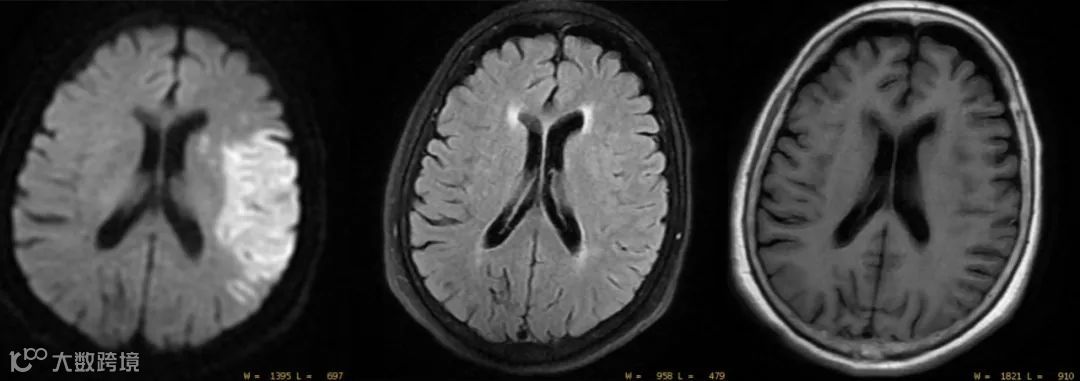

《中国脑血管病影像应用指南2019》中指出:脑卒中标准的MRI扫描序列应包括MRI(T1WI、T2WI和DWI)和MRA序列。

T2WI可更好的显示组织/病变的信号变化,特别是T2 FLAIR序列是评估病变的关键序列。

DWI是对脑卒中病灶检出最早、最敏感的序列。

不同时期的脑梗塞在MRI成像表现,如下表:

在缺血的数分钟后细胞毒性水肿导致的水分子扩散受限,DWI即可出现异常高信号,T2WI一般在6h后才出现明显的高信号,T1WI出现病灶的时间与平扫的CT相近。

所以DWI是对脑卒中病灶检出最早、最敏感的序列。

在缺血性脑卒中的超急性(发病<6h)及急性期,MRI的敏感度和特异度分别为91%和95%。DWI>FLAIR>T2WI。